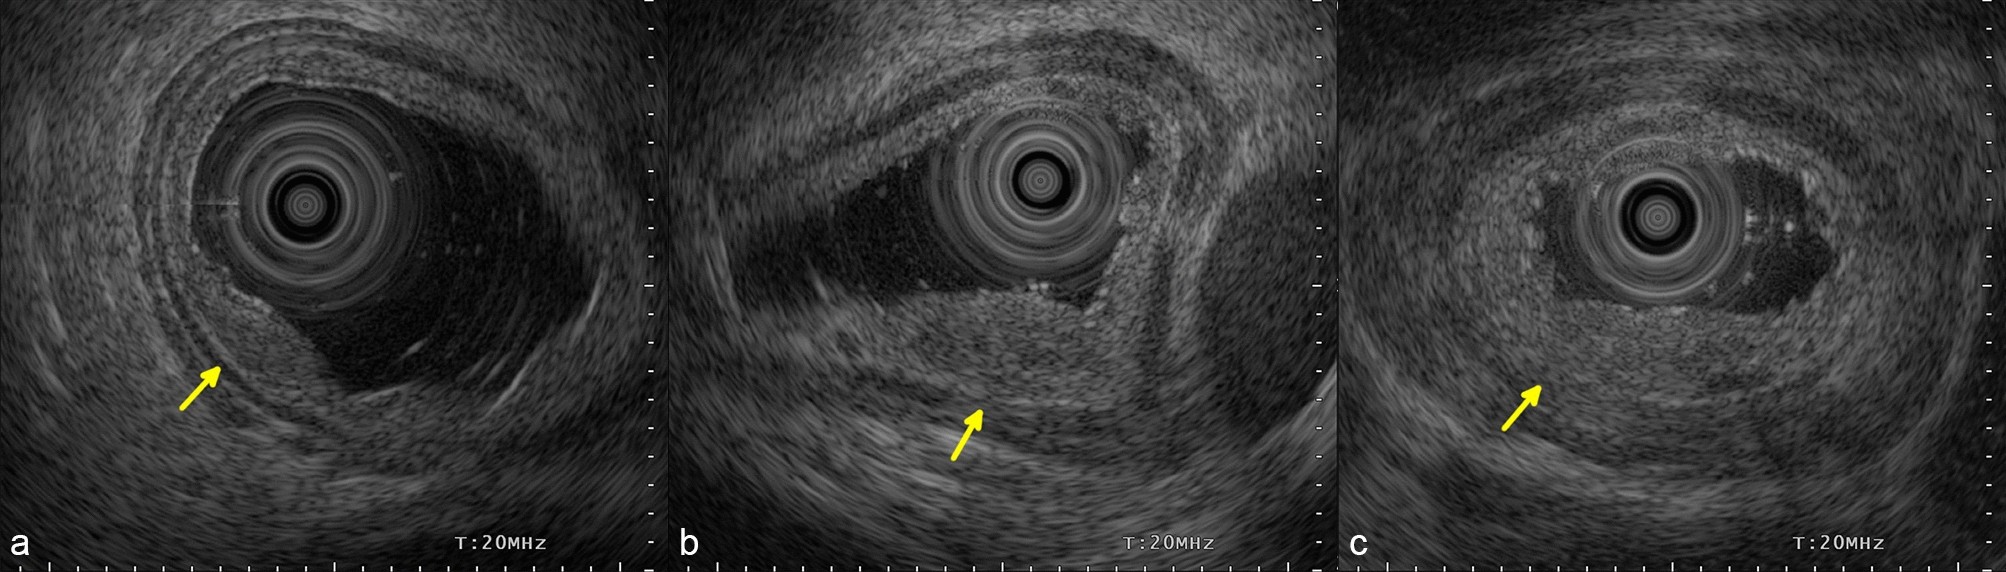

Endoscopic ultrasonography findings of local residual/recurrent cancer after CRT/RT. (a) Uninterrupted fifth layer (arrow). (b) Slurred fifth layer (arrow). (c) Ruptured fifth layer (arrow). CRT, chemoradiotherapy; RT, radiotherapy.